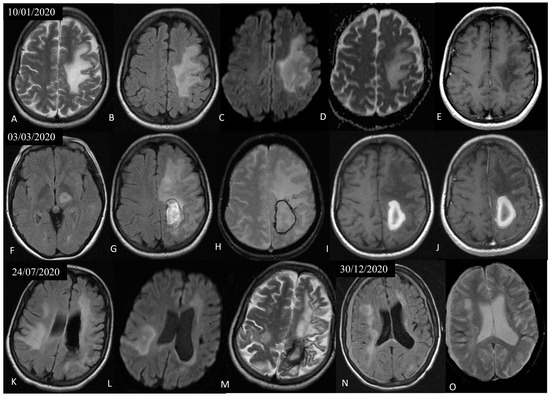

3.1. Case Presentation